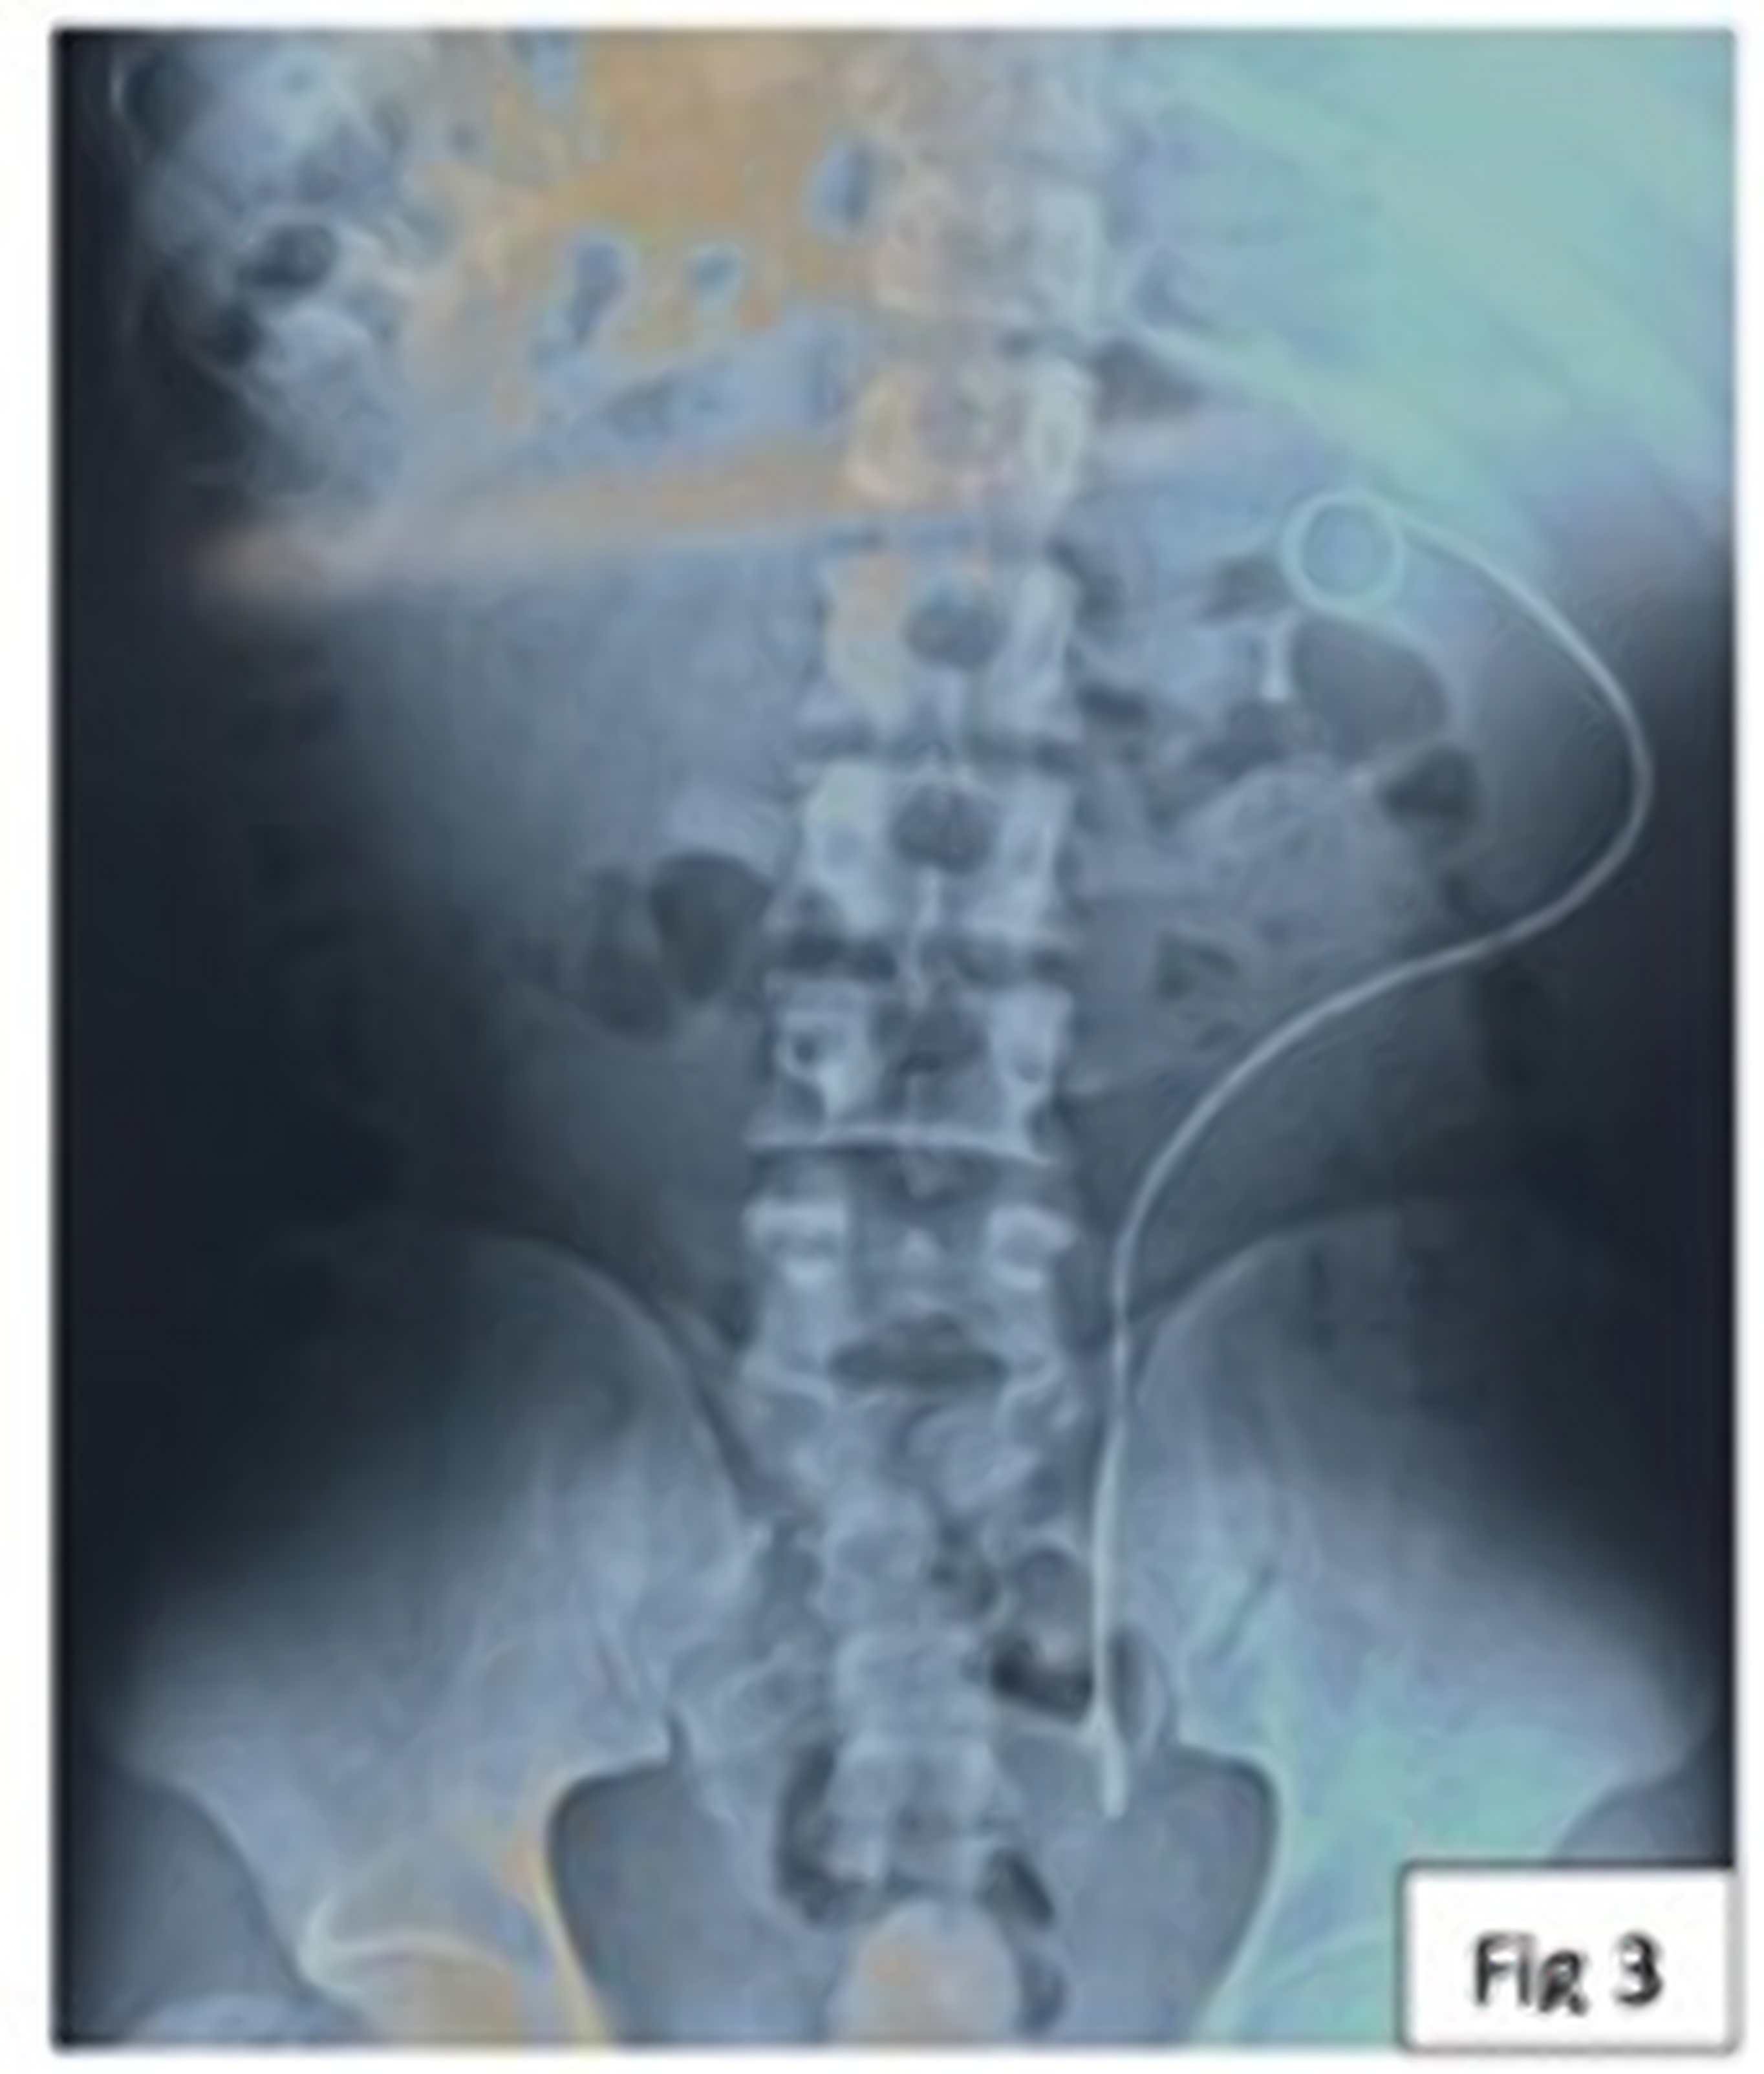

Proximal Migration of Ureteric DJ Stent: A Case Series

Background: DJ stents are routinely used in urological procedures. Rarely these may dislodge or migrate.

Case Series: Here we report proximal migration of DJ stent in three children with pelvi-ureteric junction (PUJ) obstruction treated with dismembered pyeloplasty. Ureteroscopy and retrieval of migrated DJ stents were performed in each of these patients.

Conclusion: Proximal migration of DJ stent, though rare, can cause significant morbidity and complicates it’s removal. Proper size and positioning of stent is required for pediatric patients.